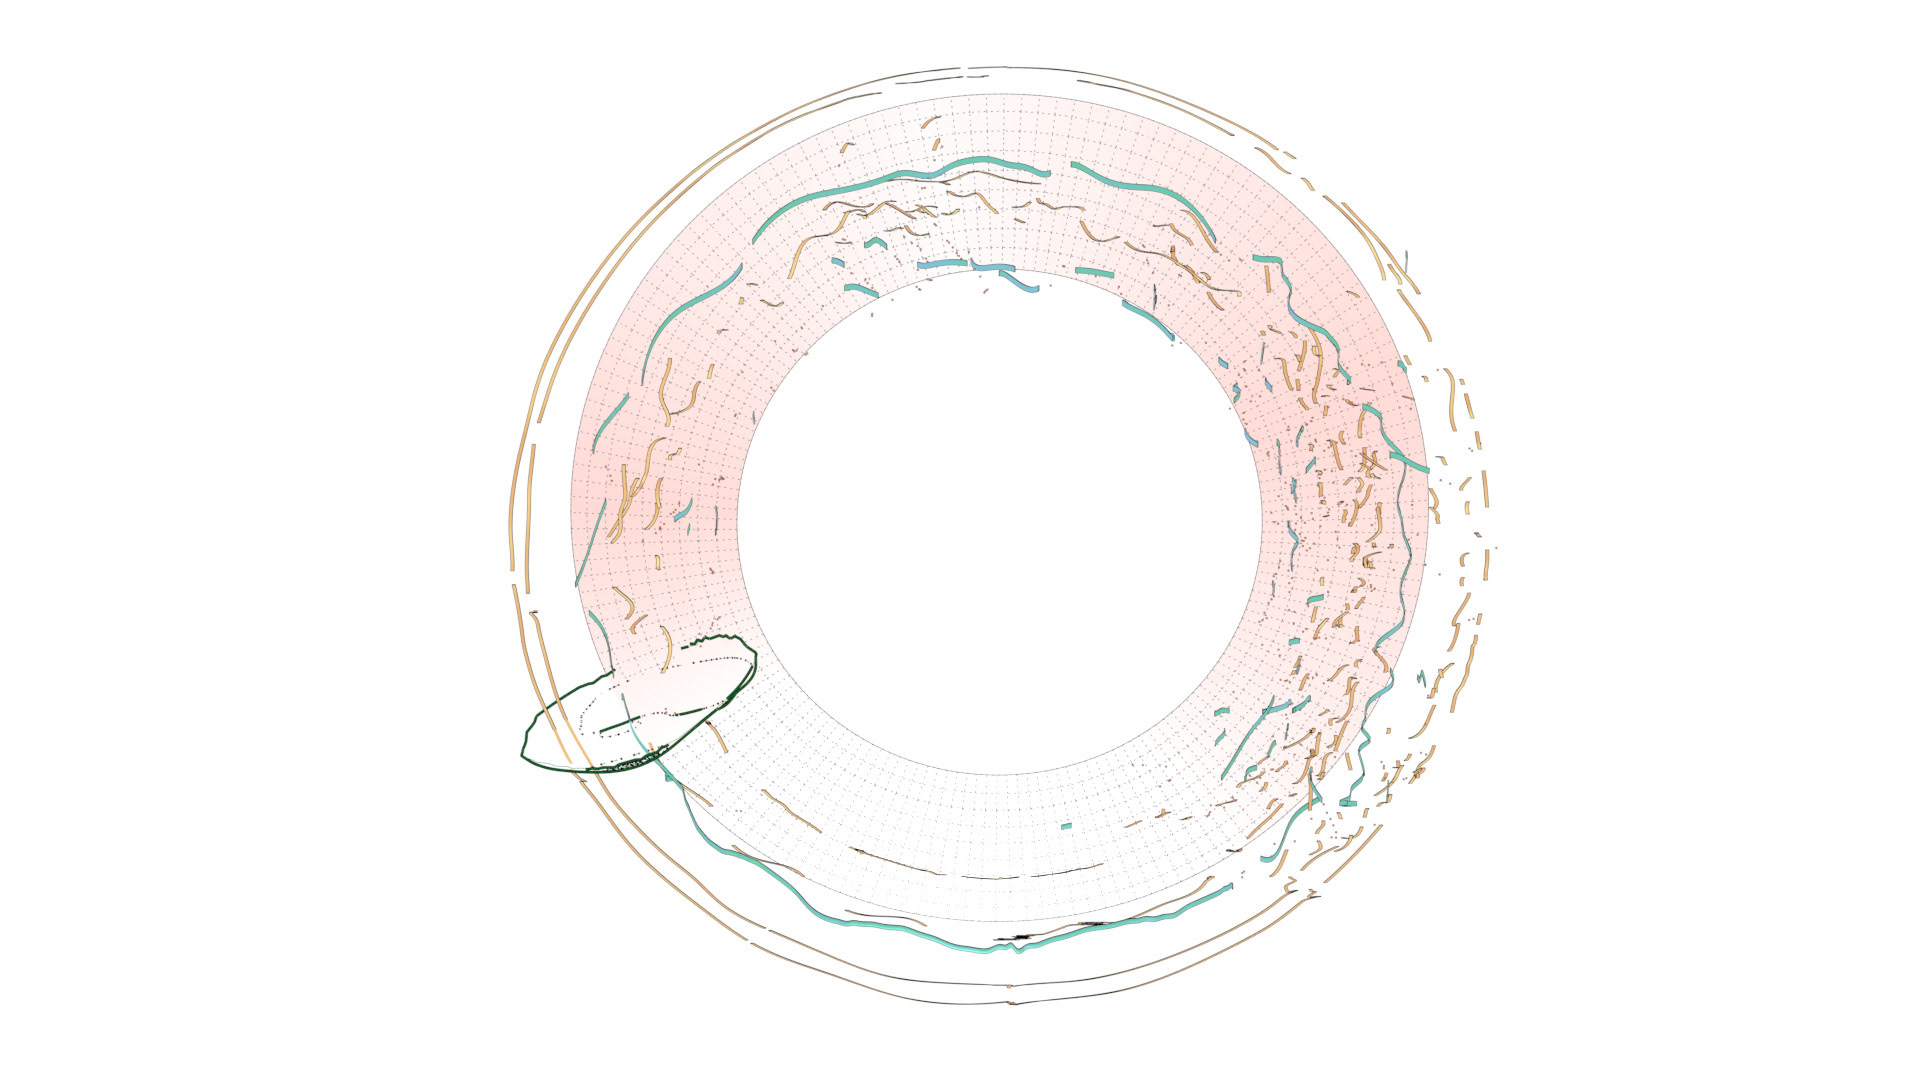

An ongoing collaboration with the Biomedical Simulation Lab (BSL), University of Toronto. In my role, I develop concept sketches and renderings that are then implemented algorithmically. The overall approach is to show turbulent flow visualizations without animation my mapping the transitions among states to carousel that corresponds to the cardiac cycle.